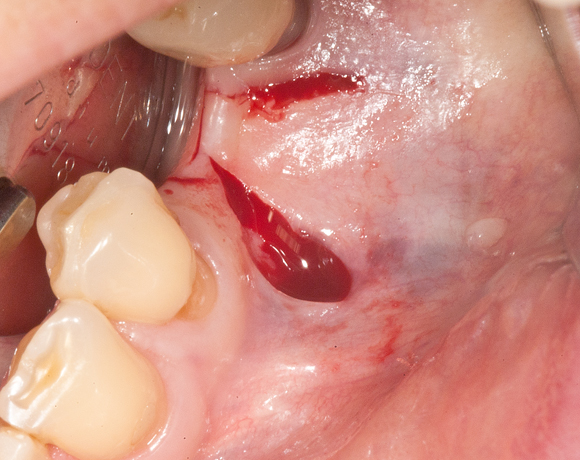

Im vorliegenden Fall war zwar eine gut Knochenhöhe vorhanden, jedoch war der Knochen zu schmal,

um Implantate aufzunehmen. Hier bietet es sich an den Knochen zu spalten, bei gleichzeitiger Insertion der Implantate und die freien Zwischenräume mit Kunstknochen aufzufüllen. Die Augmentation wird mit einer Membran abgedeckt. Die Einheilzeit beträgt sechs Monate.